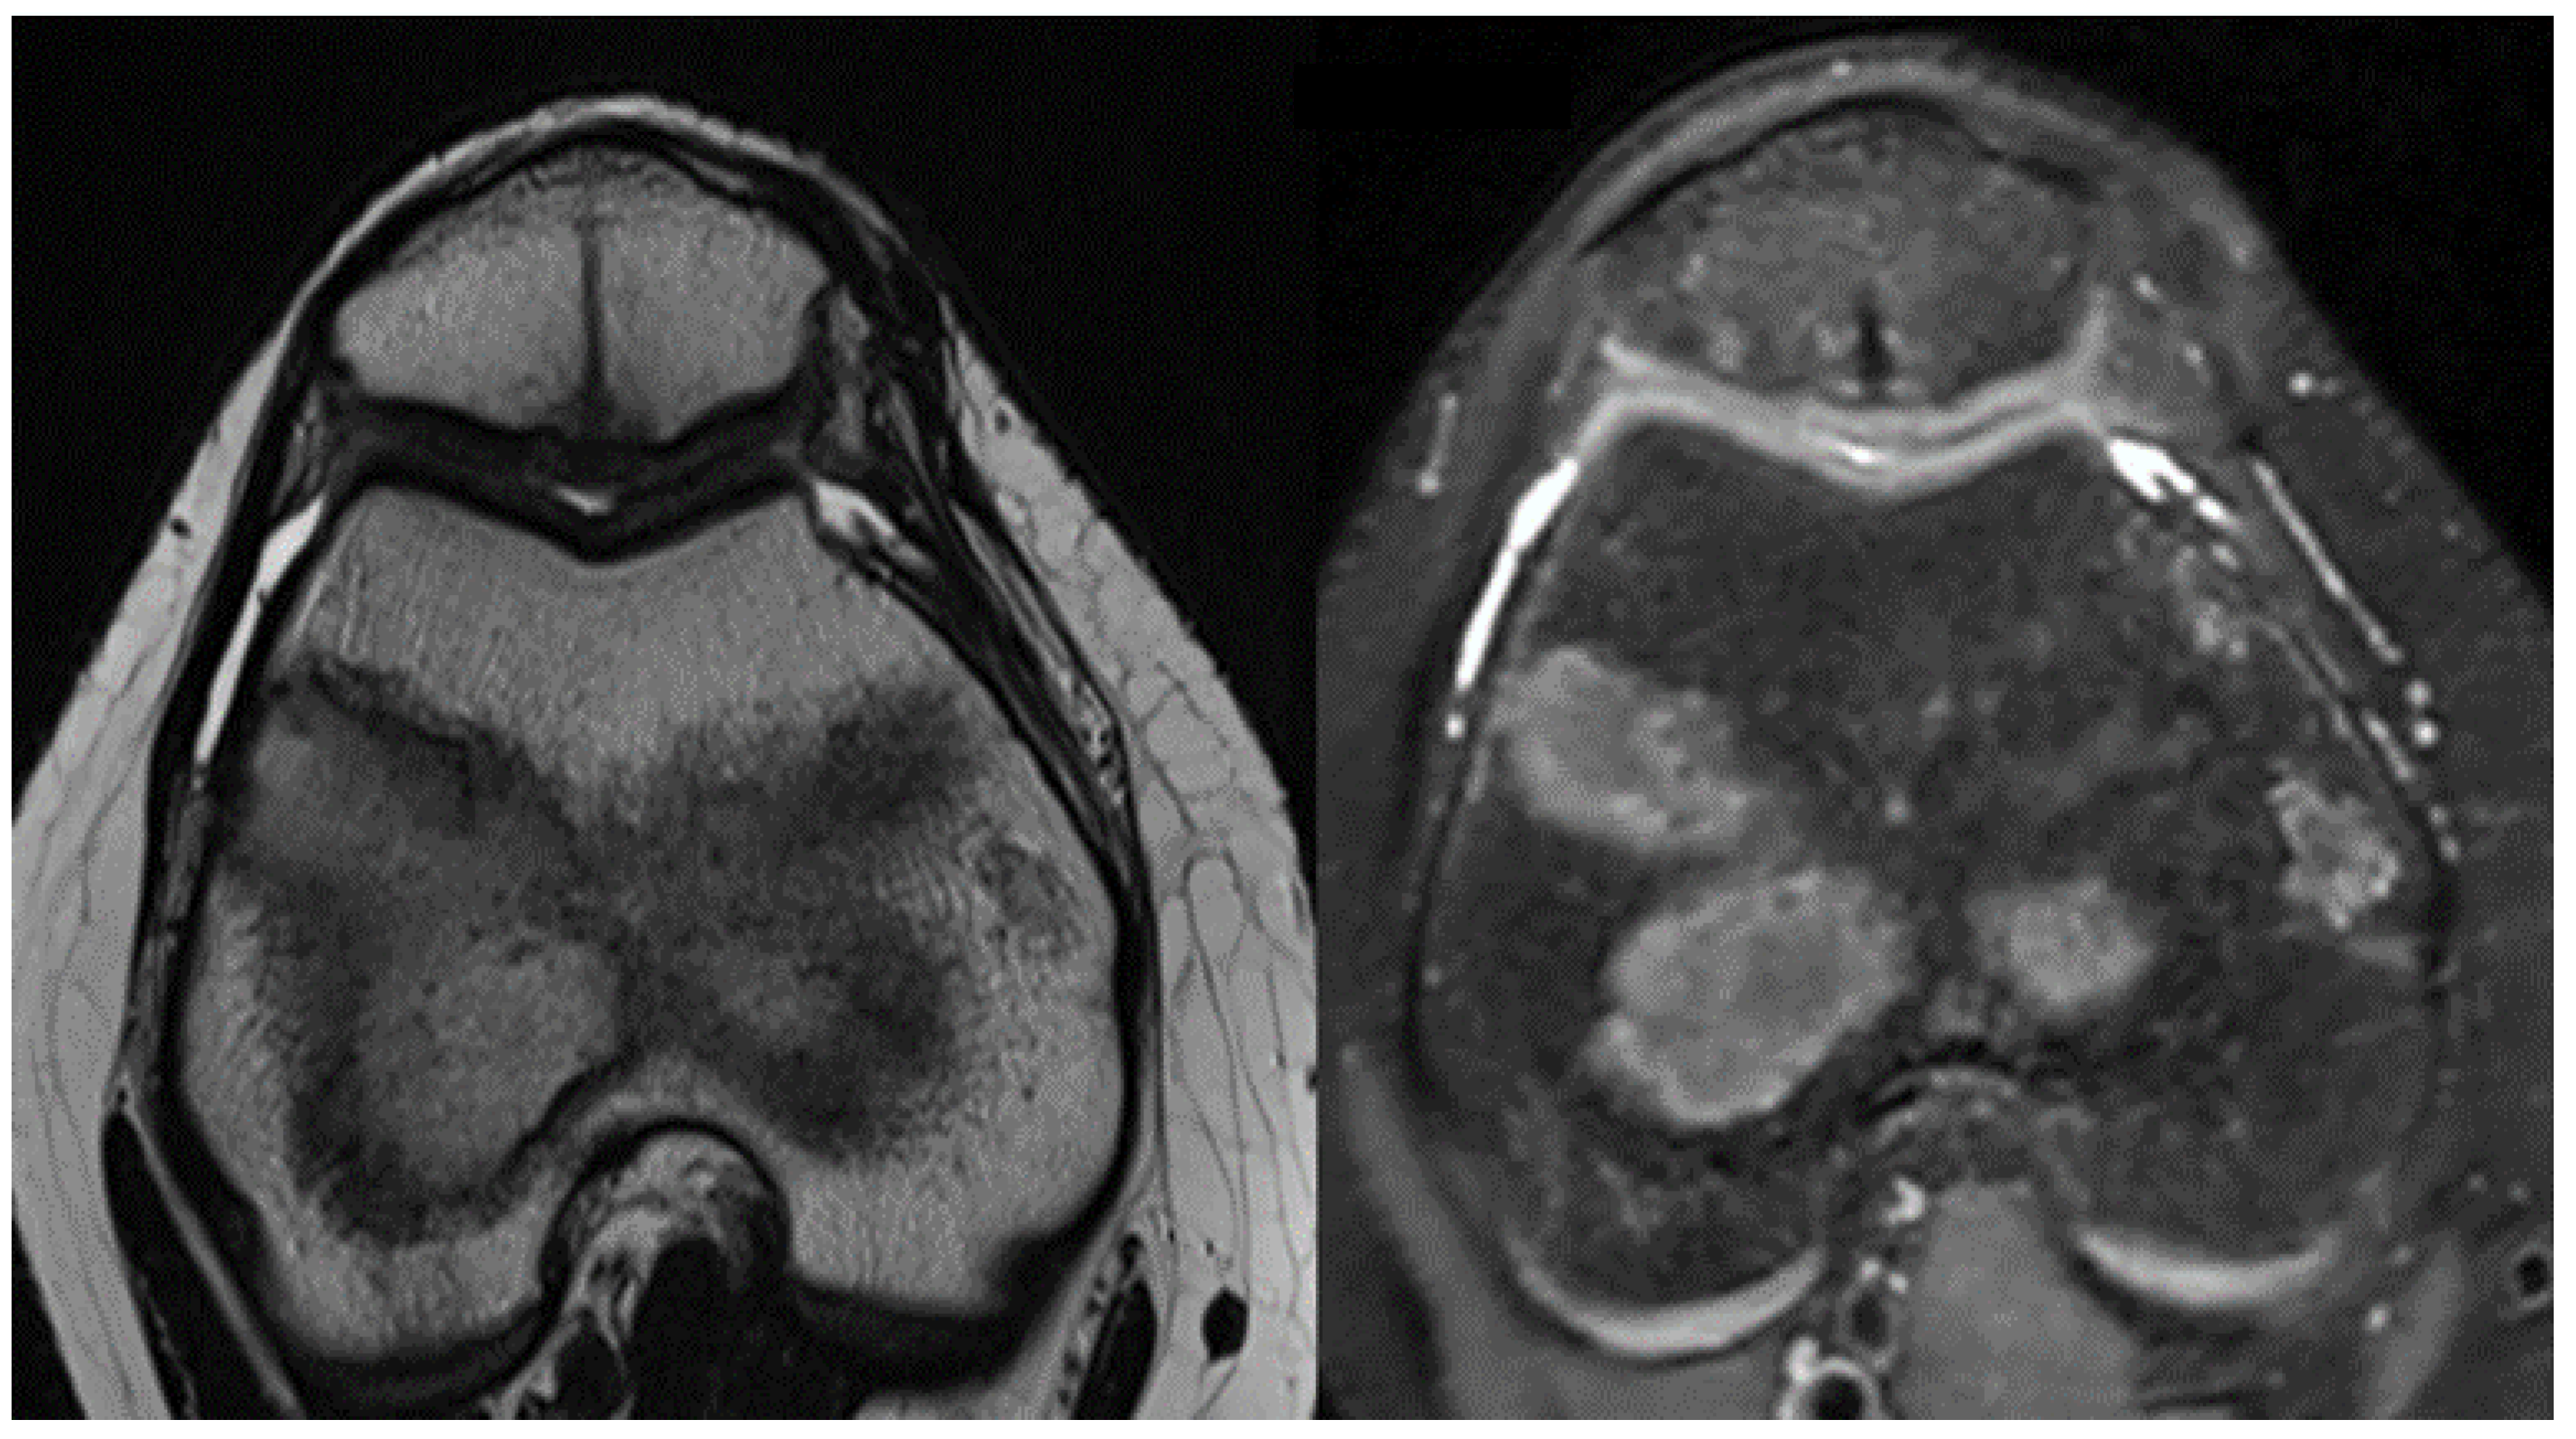

Six months after surgery, MRI scans were evaluated using the MOCART Score to categorize healing progress of the osteochondral defects (Figure 5). Recovery classifications ranged from subchondral bone exposure to full lesion coverage, indicating complete healing. The outcomes at the 6-month interval were positive, with Kujala Scale scores reaching above 90 points and MRI evaluations showing no reinsertion failures. Impressively, complete lesion filling was observed in two cases, highlighting the success of the surgical procedures [17,18].

However, scenarios demanding a parapatellar approach necessitate a more intricate, open surgical route via medial arthrotomy. This strategy caters to both the patellar fragment reinsertion and concurrent repairs of the medial patellofemoral ligament, which accentuates MRI’s indispensability, not only as first diagnostics, but also during follow-ups. This imaging modality offers unparalleled insights into treatment efficacy, reinserted fragment stability, and defect filling extents. For patients treated with fragment reinsertion, a 6-month post-surgery MRI is recommended unless clinical observations suggest fragment dislodgements [27].

Figure 5. Six months follow-up MRI images that show complete filling of the osteochondral lesion of the patella.